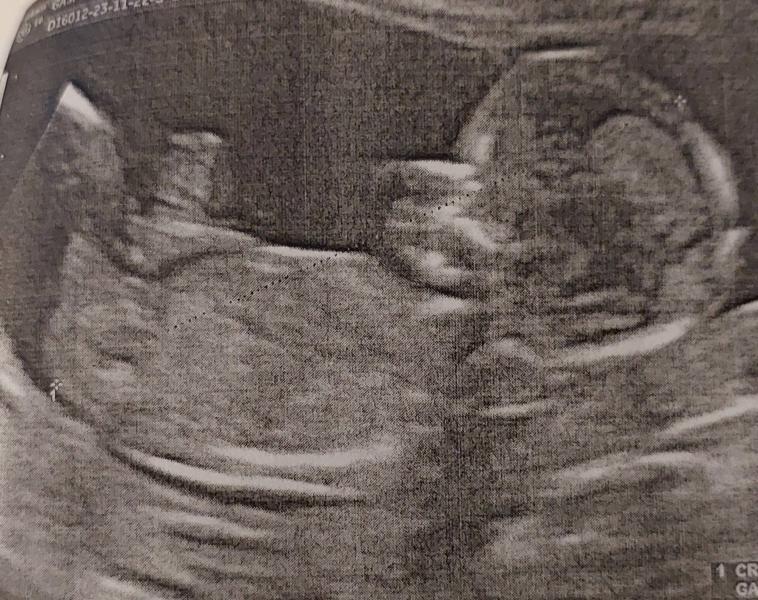

Первый скрининг пройден, все хорошо! Выдыхаю до 2 скрининга, ПДР на 27 мая, срок 13 недель

Первый скриннинг нашей малышки пройден. Все хорошо. Выдыхаю до 2 скриннинга.

Риски все минимальны.

Пдр поставили на 27 мая. Срок по месячным 13.2 нед, по узи 13.3. Прямо идеально.